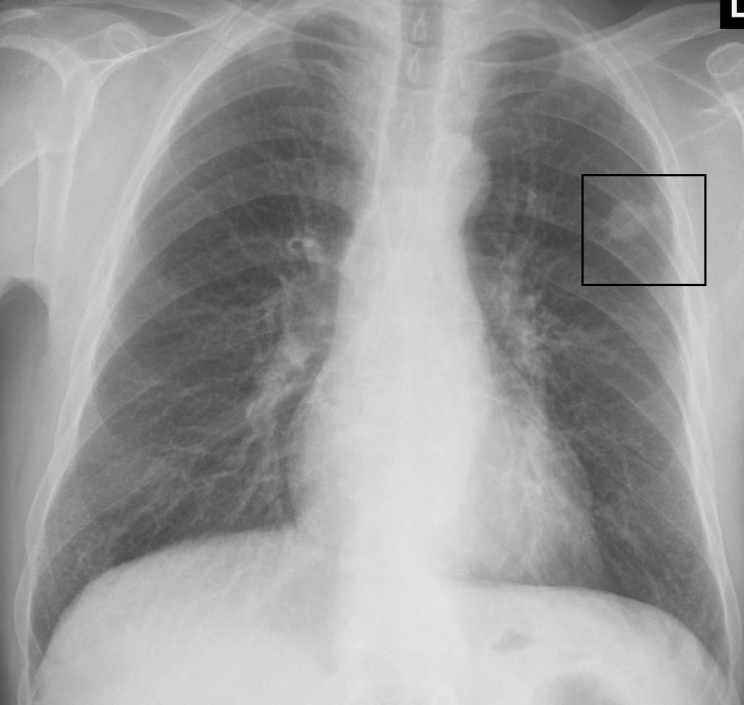

Tuberculosis in dogs and cats: what is it and how do we prevent it

Tuberculosis is known to be one of the most common diseases. For centuries now, health authorities achieved a minimized number of infections and installed safety precautions to avoid it.

However, during the last years, migration from highly infected countries such as Africa have increased the chances of getting tuberculosis and since this is a disease that affect both humans and our animals, it is important for us to know how to prevent it.

Tuberculosis is a disease caused my three different species of bacteria; all three of them can affect dogs and cats but it is very difficult for them to transmit it to other animals (we must not exclude this occurrence). The three different bacteria species are; Mycobacterium bovis especially transmitted from cows, Mycobacterium tuberculosis mainly transmitted by humans and Mycobacterium avium transmitted by birds. There are many other forms to this pathogen that may exist but they very rarely cause a disease.

These bacteria attack the pulmonary area so it is mainly transmitted through the airway. However, there might be a chance to find the bacteria on infected feces, especially in birds excretions.

These nodules will progressively grow and cause difficulties in vital processes such as respiration and digestion in our pets organism. In some cases, due to harsh non-productive coughing the nodules will break and stick to another section of the skin; this will produce a second granuloma that will continue to grow. This process will continue until the situation will be unbearable.

tube2

As we mentioned earlier, tuberculosis is very difficult to treat. However, there are some antibiotics that might be useful if we identify the infection on time (through specific tests form your vet). The main problem, is that the symptoms such as harsh cough might appear after years and at that time it might be too late to begin the treatment.